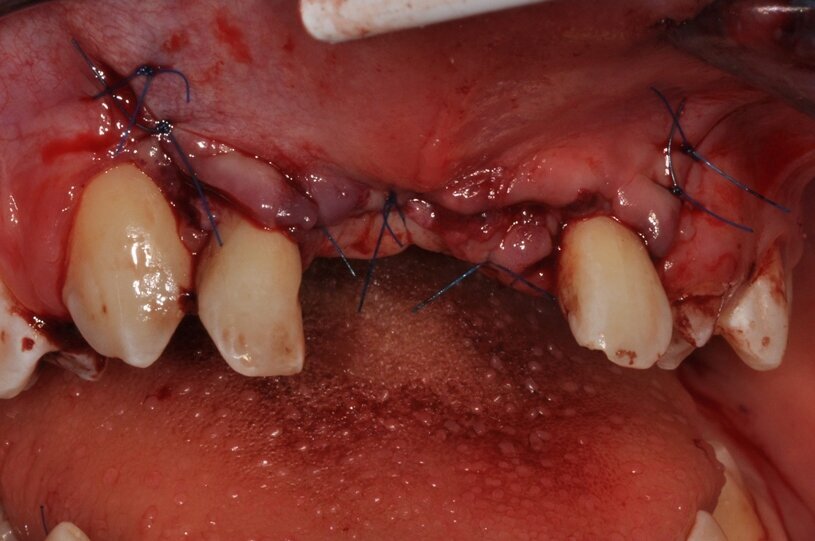

W kolejnym etapie, z wykorzystaniem tego samego lasera Nd:Yag, wytworzono skrzep w zębodołach (4 W, 20 Hz, VLP), (Ryc. 5). Ze względu na znaczącą utratę objętości tkanek miękkich, zastosowano matrycę kolagenową (Geistlich Mucograft®) nasączoną fibryną bogatopłytkową iPRF (Ryc. 6), pozwalającą na gojenie otwarte, a jednocześnie wpływającą na odbudowę szerokości dziąsła zrogowaciałego. Ranę zszyto szwami węzełkowymi z nierozpuszczalnego syntetycznego monofilamentu poliamidowego o rozmiarze 5,0 (Seralon®) tak, aby zapobiec spłyceniu przedsionka (Ryc. 7). Pacjentowi zaordynowano Doxycyclinum 100 mg (1 x 1 kaps.), Ibuprofenum 200 mg (3 x 1 tabl.), Reparil (3 x 2 tabl.), Enterol (2 x 1 tabl.) oraz zaopatrzono w szczoteczkę miękką pozabiegową (Elgydium Clinic® 7/100), płyn do płukania w postaci piany (Alfa) i zimny okład. Szwy zdjęto w 14. dniu po zabiegu. Gojenie przebiegało bez powikłań.

Ryc. 7_Stan miejscowy bezpośrednio po pierwszym zabiegu.